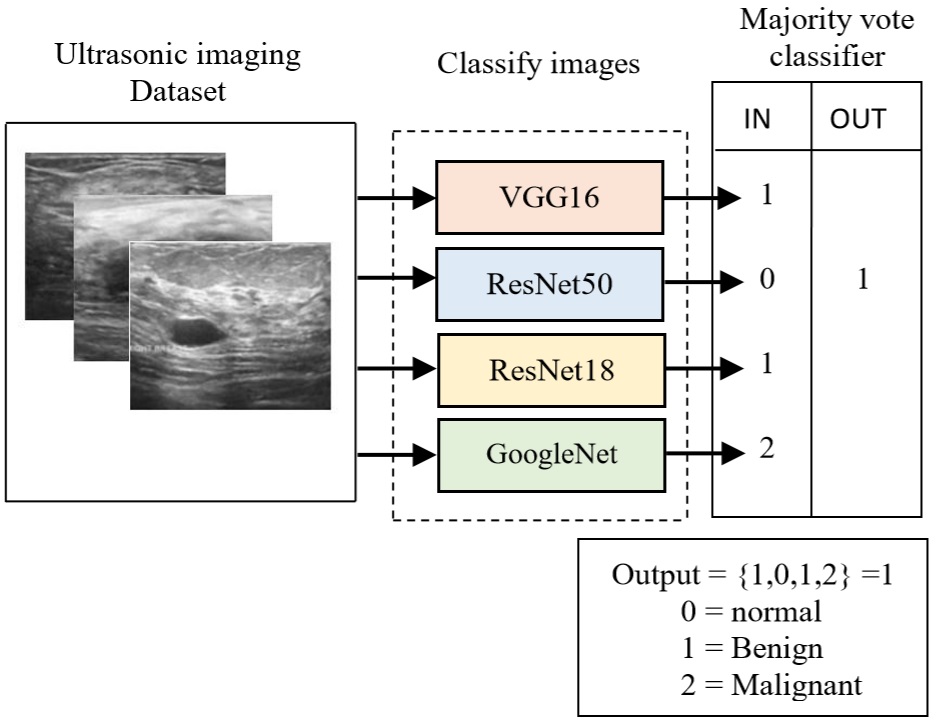

In today’s world, breast cancer is considered one of the most common types of cancer and the incident rates keep increasing by 0.5% per year. In 2020, an estimated 2.3 million women were diagnosed with breast cancer globally [1]. Breast cancer is caused by abnormal cells formed commonly in the cells of the lobules or the ducts. Cells typically have their cell growth which lets the old dying cells get replaced with healthy new cells. But, over time, these cells can mutate turning on oncogenes or turning off tumor suppressor genes. This causes the cell to uncontrollably divide producing more mutated cells and eventually forming a tumor. One of those tumors is a malignant tumor. Malignant tumors are considered cancerous and if left untreated, these malignant cells can spread throughout the body and can be life-threatening to the patient. Therefore, detecting breast cancer in the early stages can significantly increase the chances of survival. Meaning that it is vital to have proper screening methods to detect for initial symptoms of breast cancer. Various imaging techniques for breast cancer detection include mammography, ultrasound, and thermography. Each technique has its pros and cons which justify its usage. Mammography has an average specificity of 75% (25% false-positive) and an average sensitivity of 80% (20% of cancers missed). Ultrasound has an average specificity of 66% (34% false-positive) and an average sensitivity of 83% (17% of cancers missed). Thermography has an average specificity of 90% (10% false-positive) and an average sensitivity of 90% (10% of cancers missed). The average specificity and average sensitivity can be improved using artificial intelligence. In the recent years, artificial intelligence has grown in popularity with the idea of using computers to perform tasks, simple or complex, that would usually be done by a human. In some cases, these artificial intelligence machines are capable of doing tasks that are not humanly possible or do a much better job by undergoing the process of machine learning. A convolutional neural network (CNN) is a type of artificial neural network which is primarily used for image recognition and processing because of its ability to recognize patterns in images very well. Due to its ability to recognize patterns in images very well, it has gotten popular in the health department such as in the detection of breast cancer. Other studies [1, 2, 3, 4, 5, 6, 7, 8, 9, 10, 11, 12, 13, 14, 15, 16] have proposed artificial intelligence and CNN as an imaging technique because it has higher average specificity and sensitivity while also being more efficient than other imaging techniques. In this paper, we fine-tune nine neural networks pre-trained on the ImageNet dataset with the fully connected layers replaced; these networks are VGG-16 [17] , Xception [18], ResNet-18, ResNet-50 [19], DenseNet201 [20], GoogleNet [21], AlexNet [22], MobileNet [23], and Darknet19 [24]. These networks are fine-tuned and retrained on the ultrasound breast cancer images and the performance parameters such as accuracy, sensitivity, specificity, precision, and area under the curve (AUC) are computed for each of these neural networks. A combination of four fine-tuned pre-trained networks that have the highest performance are fused in a parallel architecture to perform the classification process and the voting criteria are applied in the final classification decision between the candidate object classes where the output of each neural network is representing a single vote.

For this experiment, the bagging approach is adopted to maximize performance. Each network is trained using k-fold cross-validation. The mean accuracy is measured across each fold of the trained models as seen in Figure 4. The output classification of the three selected networks is then grouped into a majority vote classifier ensemble neural network. A majority vote classifier takes the mode of the binary classifications as seen in Figure 3 [28, 29].

MATLAB Programming Language was used to train the transferring learning models. VGG16, GoogleNet, ResNet18, and ResNet50 are all CNN Models, which were pretrained on a subset of the ImageNet dataset which was used in the ImageNet Large-Scale Visual Recognition Challenge (ILSVRC), which consists of thousands of class labels and over a million images. For each network, the last three layers – fully connected, SoftMax, and classification layer are replaced with the weights randomly initialized. Each network was trained for 15 epochs with a batch size and learning rate of 8 and 0.00005, respectively. Both, stochastic ‘gradient descent with momentum (SGDM), optimizer and adaptive moment estimation (Adam) optimizers are used in the training process. The learning rate that is used for models’ training is constant, shuffle is performed each epoch. As a cross-validation method, k-fold is chosen as a strategy to combat the limited data samples. The dataset split was 20% test set and 80% training set in each fold. The K-fold cross-validation is used to ensure that each observation from the raw dataset can appear in both the training and testing set. Results were obtained using 5 different k values (1-5). Then each network is combined into a bagging ensemble neural network. This bagging ensemble uses a majority vote classifier which takes the mode of each output of the combined neural networks as seen in Figure 3. It is expected that a bagging ensemble will outperform any individual network model.